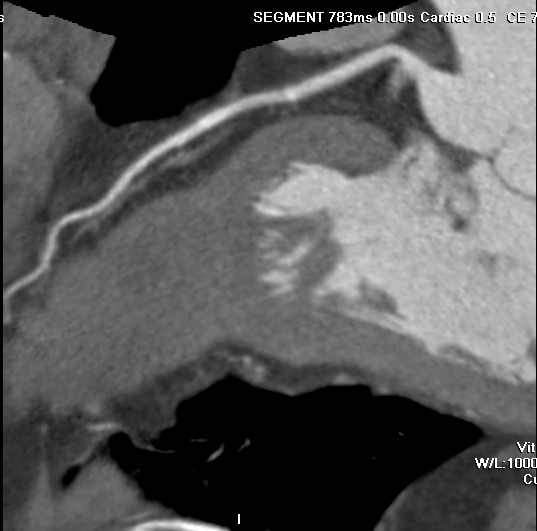

标题: CT24400:患者54岁,心前区不适进行心脏冠脉造影检查。 [打印本页]

标题: CT24400:患者54岁,心前区不适进行心脏冠脉造影检查。

患者54岁,心前区不适进行心脏冠脉造影检查。高手看看有问题没有?

图像很漂亮,好像未见异常